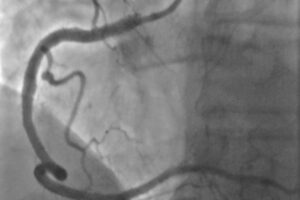

Jego specyfika polega na tym, że lekarze użyli minimalnej ilości kontrastu w trakcie angioplastyki wieńcowej, czyli naprawy zwężeń w tętnicach wieńcowych u pacjenta cierpiącego na chorobę wieńcową.

Mateusz Wiśniowski, starszy asystent w Pracowni Radiologii Zabiegowej powiedział, że procedury kardiologii inwazyjnej wymagają podania środka kontrastowego, co wiąże się ze zwiększonym ryzykiem uszkodzenia nerek, a jednym z rozwiązań, które pomaga ochronić nerki pacjenta jest wykonanie zabiegu techniką minimalnej objętości kontrastu, bądź nie używania środka kontrastowego w trakcie zabiegu.